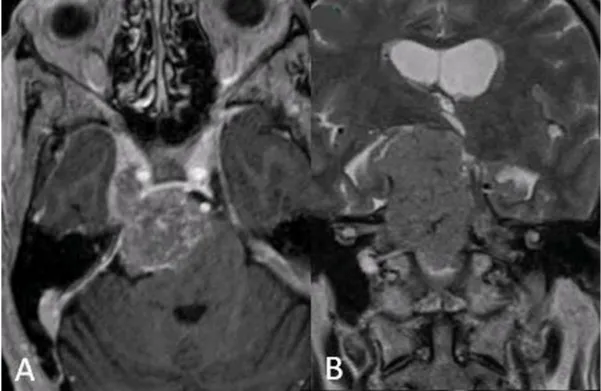

2023年,48岁的工程师老陈因复视和行走不稳就医,3.0TMRI显示右侧岩斜区有一枚3.5cm脑膜瘤,像章鱼般包绕基底动脉并压迫面神经。这个消息让他瞬间陷入恐慌——岩斜区,这个由颞骨岩部与斜坡组成的颅底核心区域,密集分布着12对颅神经中的7对、椎基底动脉系统,曾被称为神经外科的“死亡三角”。但在INC巴特朗菲教授团队的显微手术下,老陈不仅实现肿瘤全切,术后3个月复视消失,步态也恢复正常。这个案例印证了一个关键事实:岩斜区脑膜瘤的治疗,早已从“束手无策”进化到“精准破局”,但前提是对其解剖特征与治疗策略的深度理解。

老陈的手术持续10小时,巴教授团队在显微镜下完成300余次显微操作,成功剥离包绕基底动脉的肿瘤包膜。术后第7天,他就能自主行走;3个月后,复视完全消失,听力较术前提升30%。这个案例的关键在于:

精准评估:3D-TOFMRA显示肿瘤与基底动脉粘连面积<50%,具备手术全切条件;

技术整合:乙状窦后入路联合神经内镜,既暴露肿瘤主体,又清除内听道底的微小病灶;

全程管理:术后早期启动面神经康复,配合质子放疗巩固效果,杜绝残留病灶复发。